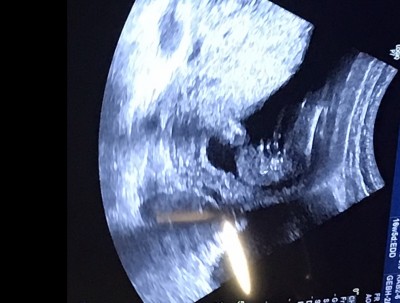

17 haftalik kiz mi erkek mi sizce ☺️

Kiz o bebek mi bacak arasi mi

Ki eger bacak arasysa kizdr buyuk ihtimlle

Bacak arasi :))

Pipi gorunmuyo bacim kiz bence :)

Kordon bacim :)

Kordonun önünde de ince bişey var ama o pipi için biraz uzun ve ince dimi

Dogru bildin. Kiz